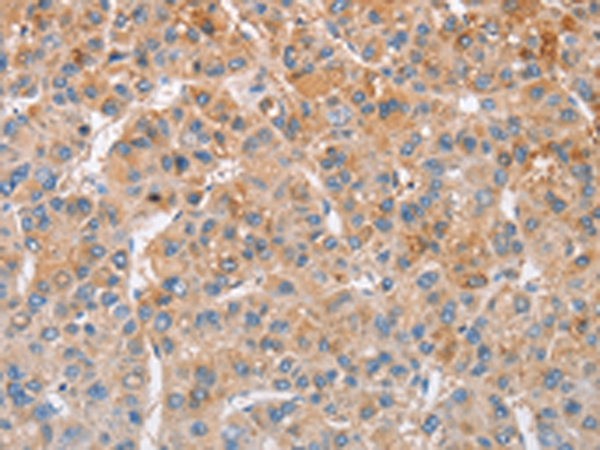

分类: 科研抗体货号: P07972别名: SHIK; SgK495应用: IHC反应种属: Human, Mouse, Rat